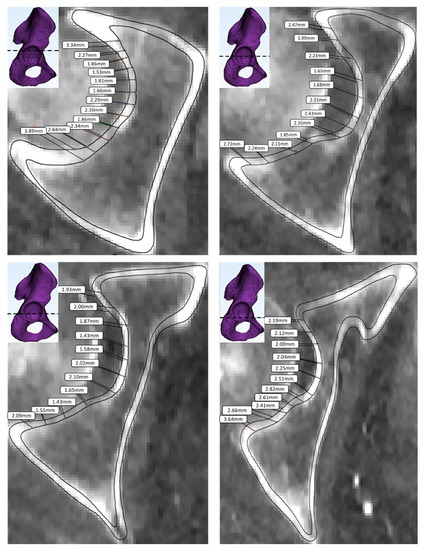

3.3. Bone Failure Type

| Conventional flooring material | Rigid *, ceramic tile, ethylene-vinyl acetate, linoleum, concrete, plywood, asphalt pavement, agglomerated cork |